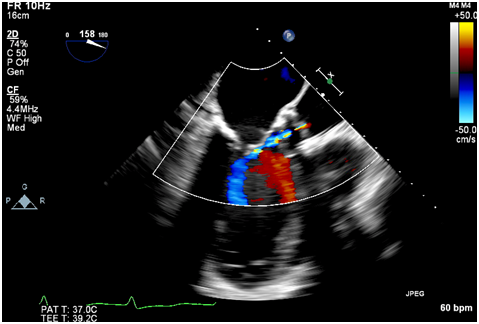

Immediately after the prosthetic valve deployment, intraprocedural TEE revealed a 20 x 9.5 mm mobile echo density attached to the ventricular side of the strut along the right coronary cusp. The structure intermittently prolapsed through the leaflets of the newly placed valve prosthesis during systole (Figure 1A, 1B). However, only mild (1+) central aortic regurgitation was noted (Figure 2). There was no left ventricular outflow tract obstruction and the prosthetic valve leaflet excursion was otherwise normal. The peak and mean aortic valve gradients were 7 and 4 mm Hg respectively post deployment.

Figure 2 Intraoperative TEE post deployment showing mild central aortic insufficiency.